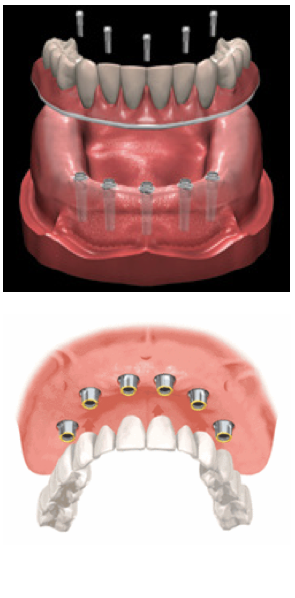

Dental implant prostheses are essentially replacement teeth that are attached to or supported by implants that are surgically placed in the jawbone. The most common implant prostheses include: Single Prosthesis – A crown attached to its own implant, used to replace a single missing tooth. Medical implants are devices or tissues that are placed inside or on the surface of the body. Many implants are prosthetics, intended to replace missing body parts. Other implants deliver medication, monitor body functions, or provide support to organs and tissues.

- Dental Implants